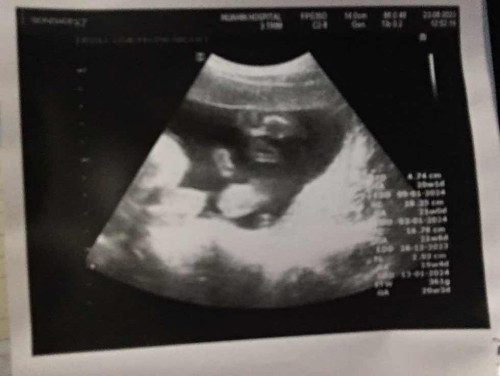

ตอนนี้ท้องได้20สัปดาห์ค่ะไปหาหมอมาลูกน้ำหนักตัว361กรัมนี่ถือว่าตัวเล็กไหมคะ แล้วอยากทราบว่าในภาพ ผญ.หรือผช. ดูจากตรงไหนคะ

นน.น้องตามเกณฑ์ดีค่ะแม่ ถ้าเทียบ 20 วีค นน.น้องจะอยู่ประมาณ 300 ++ กรัมค่ะ ส่วนเพศต้องให้หมอดูให้นะคะ